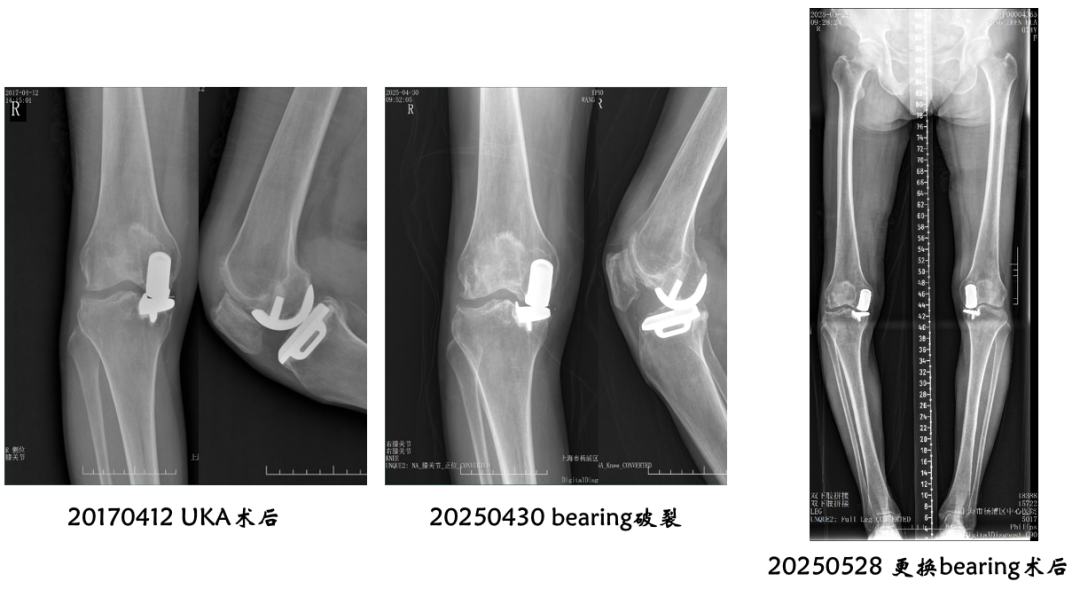

病例展示1

病例1:Bearing 前脱位

病例1:Bearing 前脱位的处理

病例展示2

病例2:Bearing 破裂( X-ray正位)

解读:两个点都在内侧

病例2:Bearing 破裂( X-ray侧位)

解读:股骨假体与胫骨假体间隙还存在,在图像放大4倍情况下,才依稀看到模糊的点.

病例2:Bearing 破裂

病例2:Bearing 破裂的处理